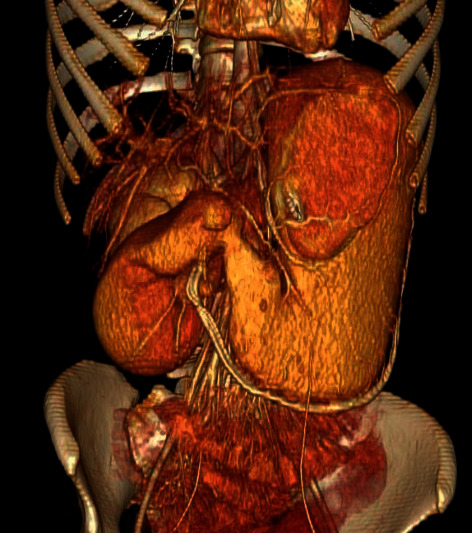

Superior mesenteric artery (SMA) syndrome is a rare etiology of upper gastrointestinal obstruction. The measured angle between the SMA and the aorta is typically between 38 and 65° and maintained by mesenteric fat. Excessive fat loss can lead to intestinal obstruction due to an exaggerated acute angularity of the SMA, compressing the third part of the duodenum. We present a 22-year-old female with a history of aplastic anemia, status post bone-marrow transplant, who presented with intractable nausea and had confirmed SMA syndrome on CT angiography. Subsequently, the patient underwent nasogastric decompression and successful laparoscopic duodenojejunostomy.

摘要肠系膜上动脉症候群是一种罕见的上消化道梗阻病因。SMA与主动脉之间的测量角度通常在38°至65°之间,由肠系膜脂肪维持。由于SMA的急性角度过大,压迫十二指肠的第三部分,脂肪的过度减少可导致肠梗阻。我们报告一位22岁的女性,有再生障碍性贫血史,骨髓移植后的状态,她表现为顽固性恶心,CT血管造影证实为SMA综合征。随后,患者接受了鼻胃减压术和成功的腹腔镜十二指肠空肠吻合术。